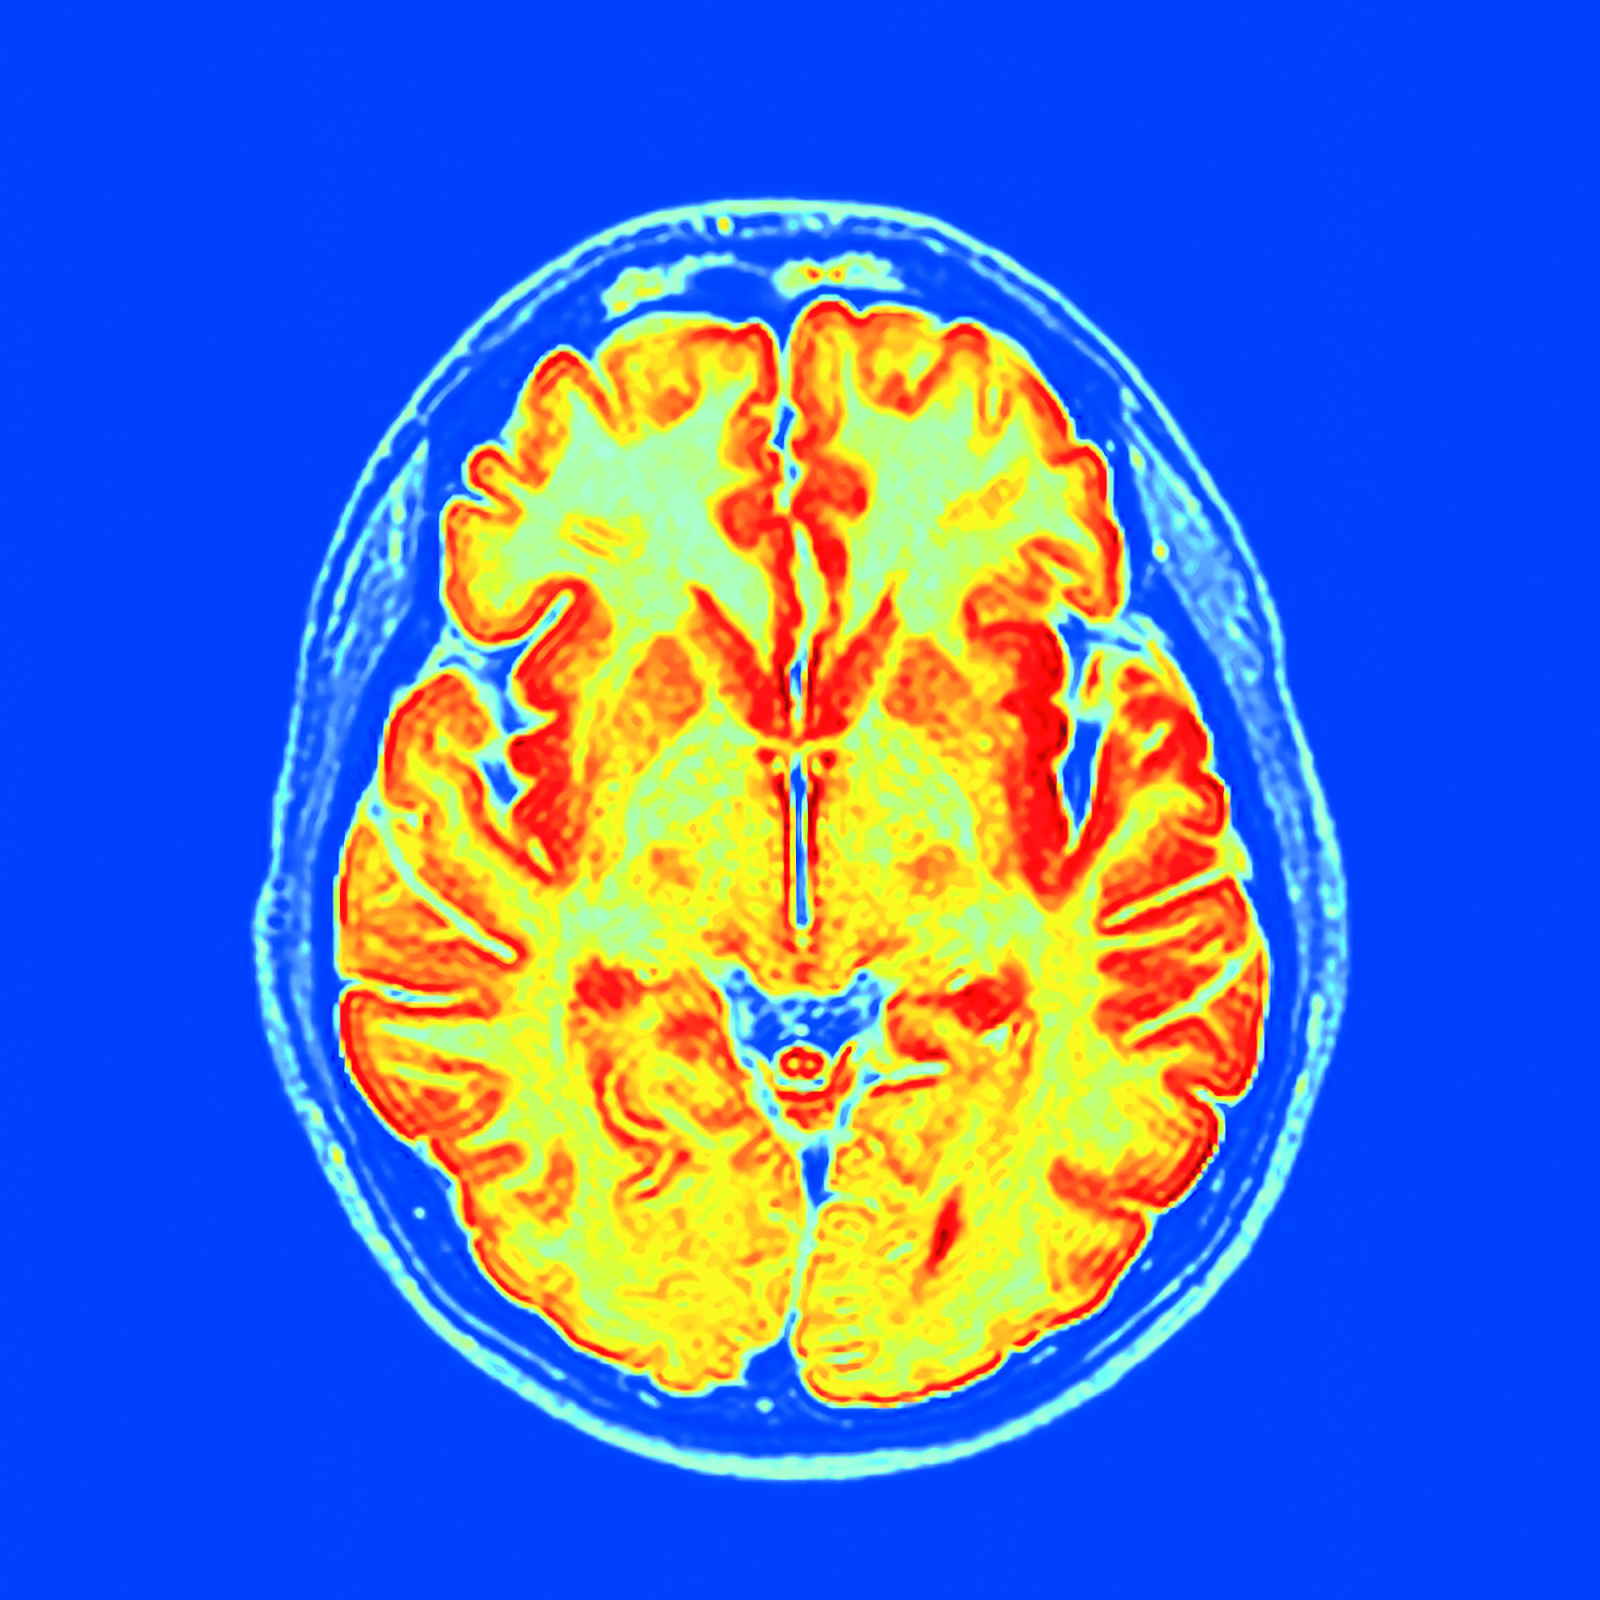

Συγκεκριμένα η ερευνητική ομάδα ανέπτυξε ένα δημόσια διαθέσιμο εργαλείο το οποίο μπορεί να «δει» σε μία και μόνο μαγνητική τομογραφία του εγκεφάλου ενός μεσήλικου τον ρυθμό της γήρανσης του εγκεφάλου του (και όχι μόνο) και να προβλέψει τον κίνδυνο άνοιας και άλλων νόσων του γήρατος ακόμη και δεκαετίες πριν από την εμφάνισή τους.

Το νέο εργαλείο που ονομάστηκε DunedinPACNI, εκπαιδεύθηκε ώστε να εκτιμά τον ρυθμό της γήρανσης αναλύοντας μία και μόνο μαγνητική τομογραφία του εγκεφάλου, η οποία είχε διενεργηθεί σε 860 συμμετέχοντες της Dunedin Study όταν εκείνοι ήταν 45 ετών.

Στη συνέχεια το DunedinPACNI χρησιμοποιήθηκε για την ανάλυση μαγνητικών τομογραφιών του εγκεφάλου και άλλων ατόμων από το Ηνωμένο Βασίλειο, τις ΗΠΑ, τον Καναδά και τη Λατινική Αμερική.